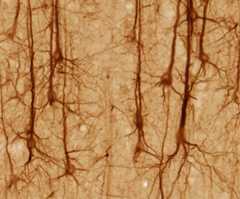

Pyramidal neurons in the cerebral cortex stained with a monoclonal antibody to neurofilament protein (SMI32): The somas (bodies) appear almost triangular with multiple dendrites attached, which are connected to long axons.

Image: “SMI32-stained pyramidal neurons in cerebral cortex” by UC Regents Davis campus. License:CC BY 3.0